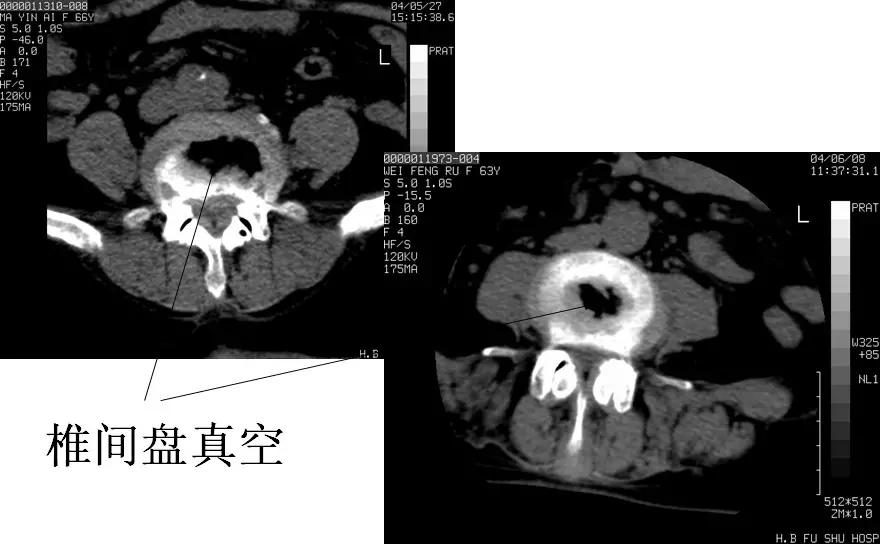

膨出的椎间盘外周可有弧形钙化,有时可显示椎间盘“真空”征和髓核钙化。